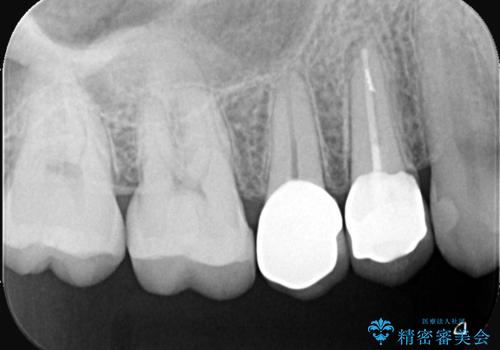

補綴物は残存歯質量からクラウンとしました。

・生活歯髄療法 40,000円(税抜き)

・仮歯 10,000円(税抜き)

・オールセラミッククラウン(スタンダード)110,000円(税抜き)